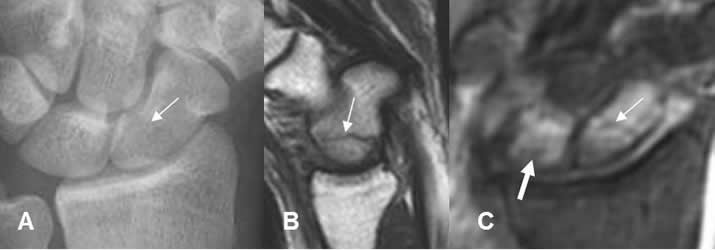

Fig 24. Fractura del escafoides.

A: Rx AP. Fractura transversa del escafoides, en su tercio medio.

B: RM sagital en T1. La fractura se identifica, como línea hipointensa.

C: RM coronal en STIR. Edema y fractura del escafoides (Flecha delgada). Adicionalmente se aprecia contusión del semilunar (Flecha gruesa).